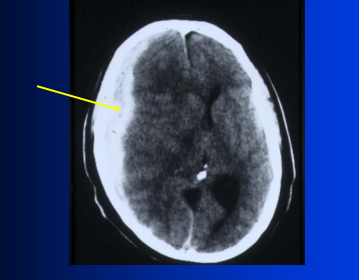

see infarct in posterior temporal lobe on left

arrows point to penumbra; tissue on the margins of an infarct that is at risk for dying

goal is to rescue penumbra tissue with acute therapy